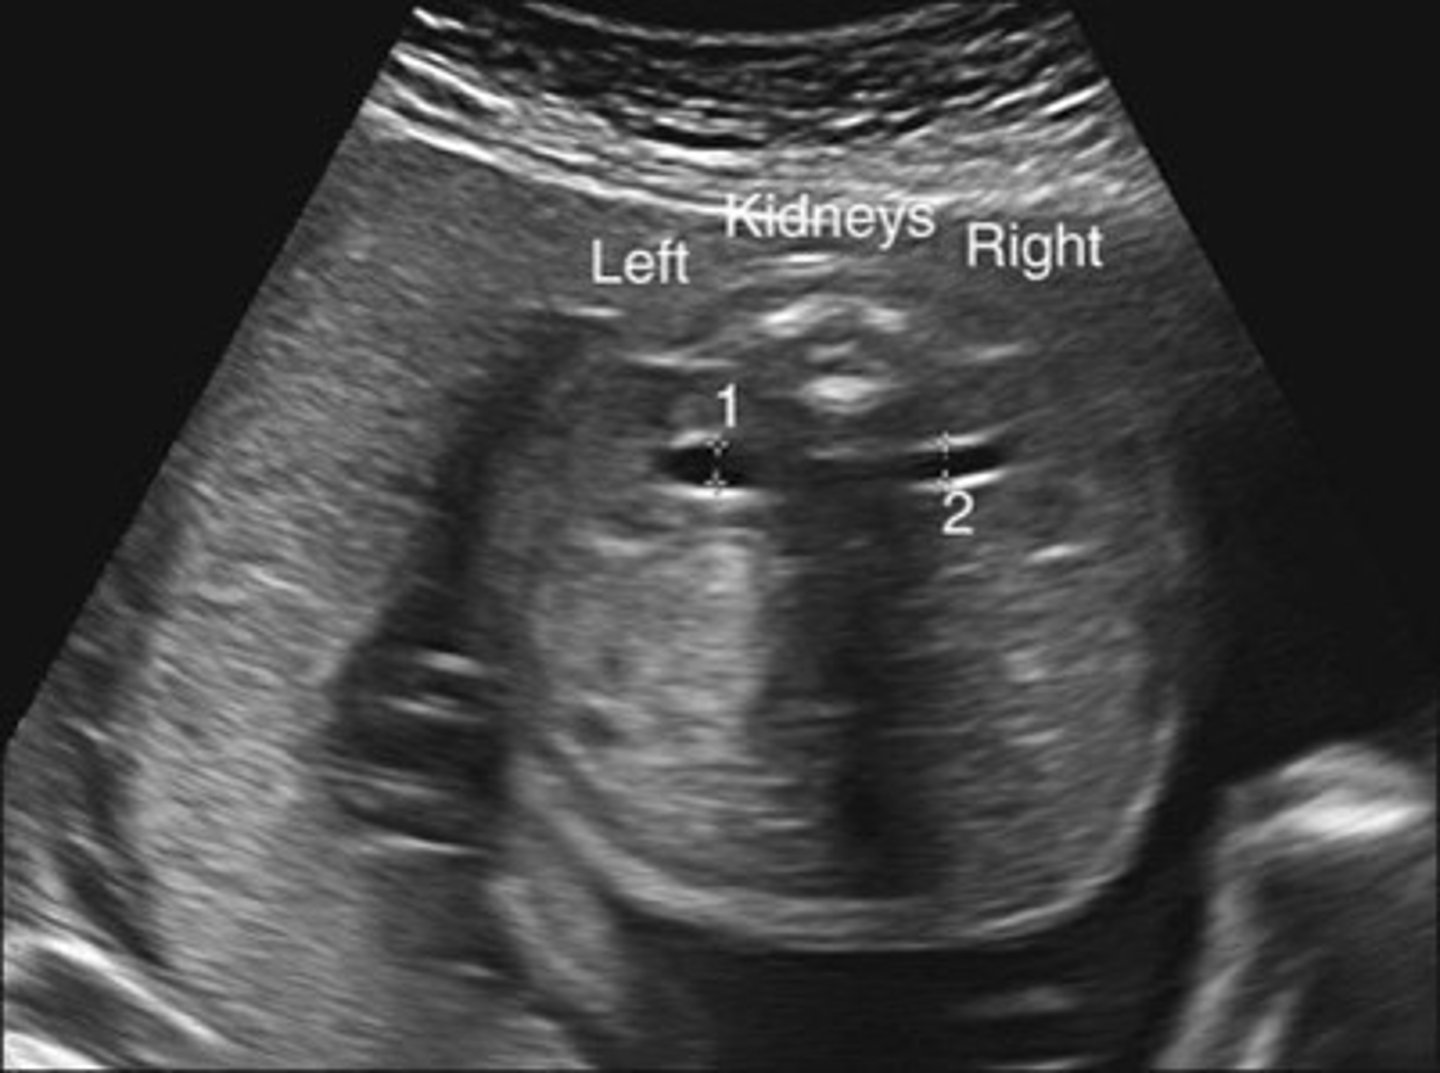

Grade 0 Hydronephrosis

Normal kidney

Grade 1 Hydronephrosis - Pyelectasis

Fluid within renal pelvis, but small enough to be considered insignificant/within normal range

Grade 2 Hydronephrosis

Pelvis is > 10 mm

Few calyces seen

Cortex is normal

Grade 3 Hydronephrosis

Marked dilation of calyces

Grade 4 Hydronephrosis

Mild thinning of cortex

Grade 5 Hydronephrosis

Severe thinning of cortex